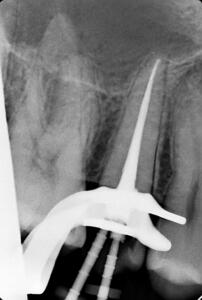

Клинические случаи в эндодонтии